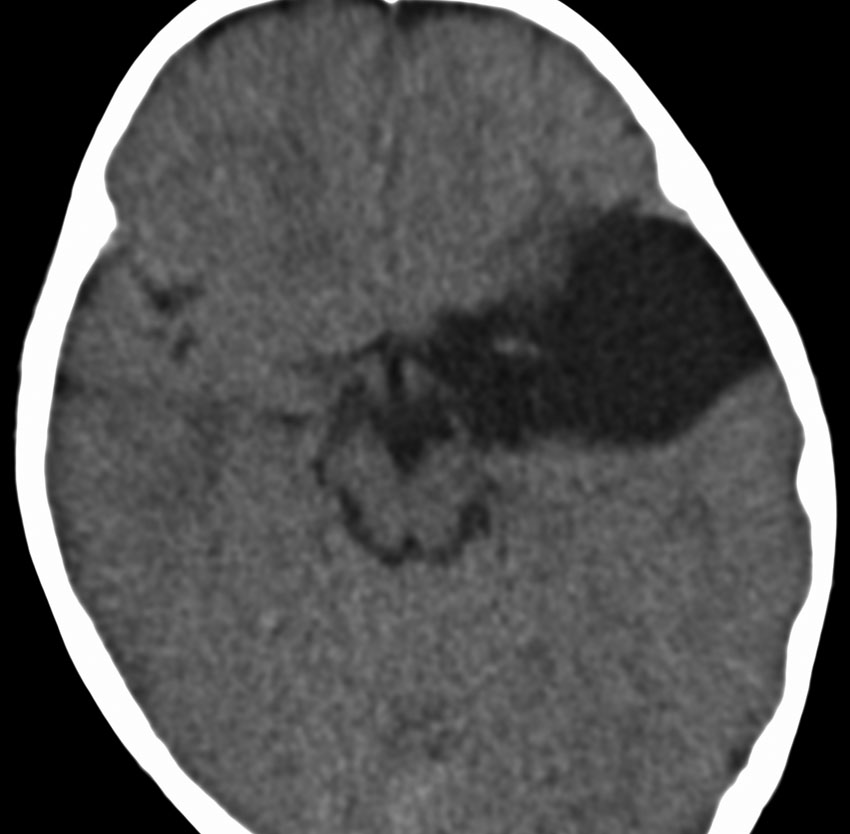

中頭蓋窩・症候性・くも膜のう胞

60代の女性で偶然発見された大きなクモ膜のう胞です。経過とともに少しづつ増大して,ふらつき,眠気,気分の落ち込みなど抑うつ状態となりました。抗うつ薬の投与が開始され増量されましたが精神症状は悪化して何もできなくなりました。おそらく右側頭葉症状として抑うつ症です。内視鏡ですと脳に損傷が生じますから,開頭顕微鏡手術で,クモ膜のう胞を脳底槽へ開窓しました。術後に症状は消失して5年になりますが,抗うつ薬なしで元気にしています。

もしかするとこれは,巨大な choroidal fissure cystかもしれません。